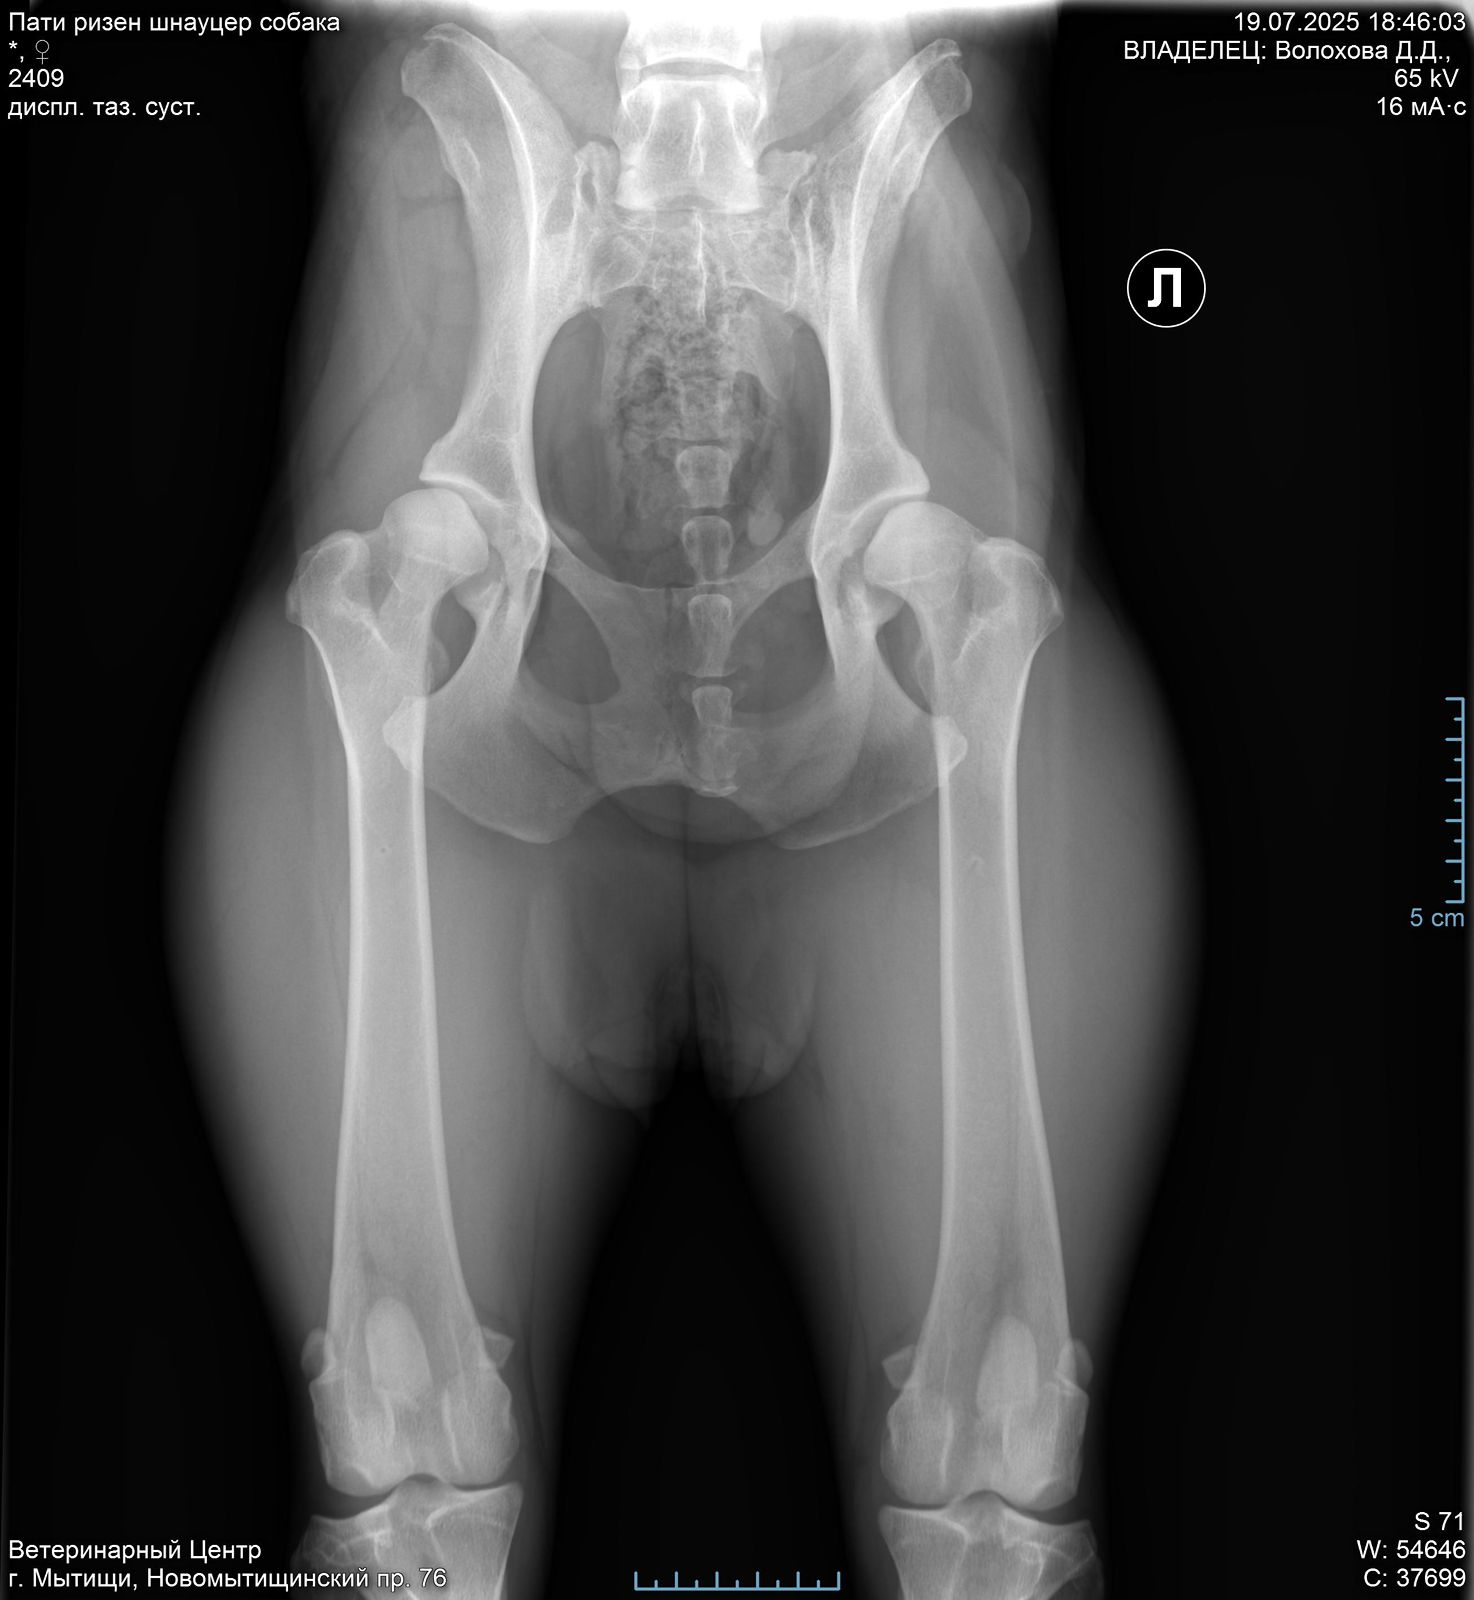

Задние ноги не идеал, но портить жизнь не должны.